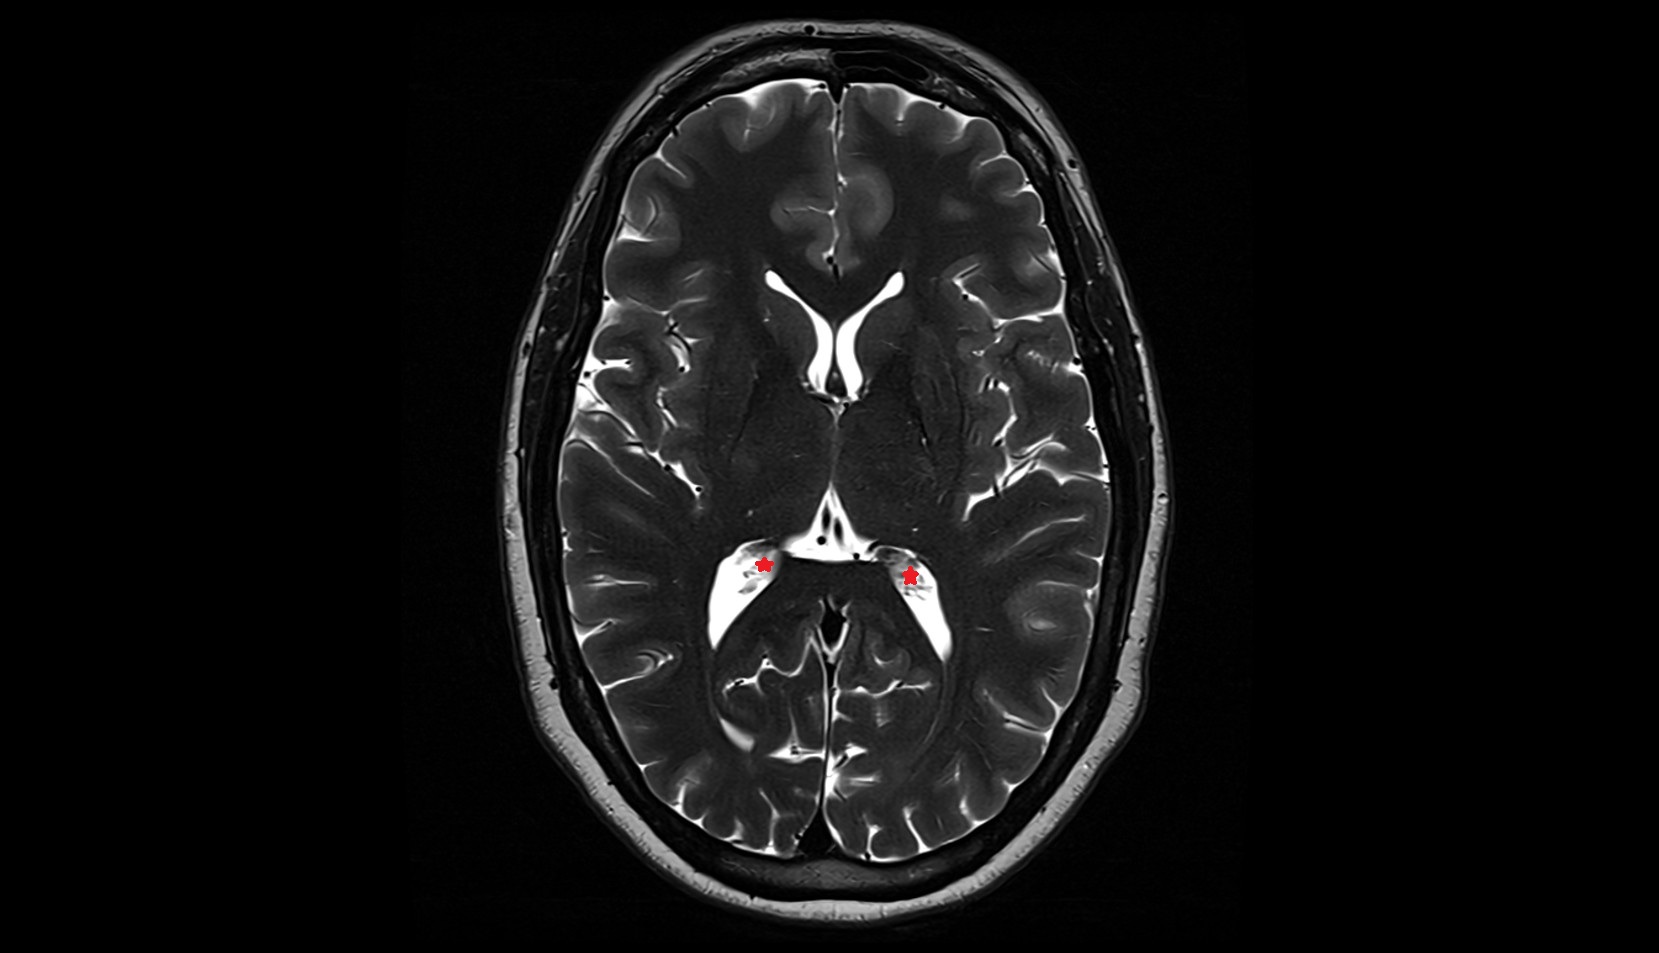

- Body of hippocampus

- Head of hippocampus

- Tail of hippocampus

- Hippocampus